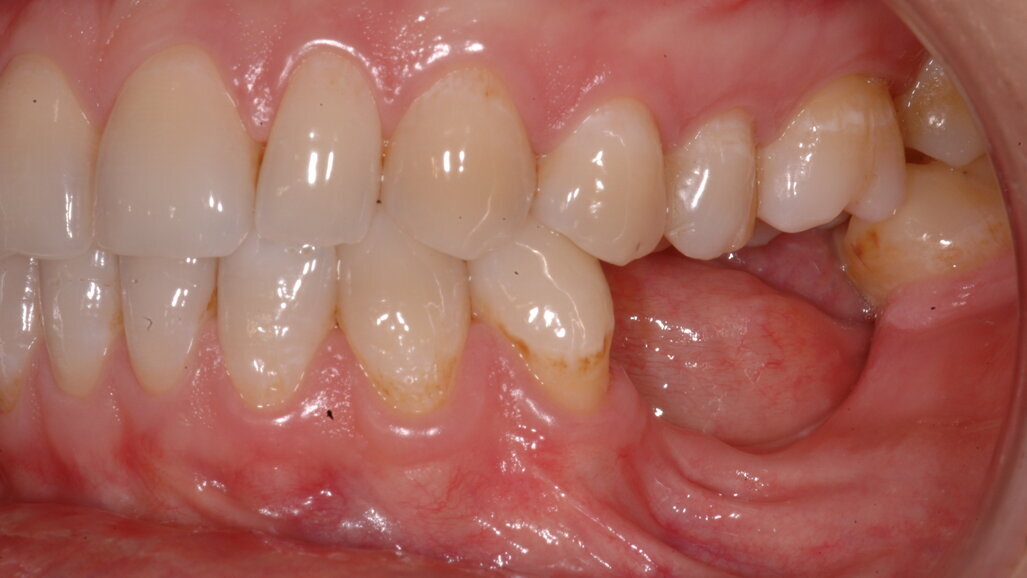

Una paziente di 35 anni si presentò alla nostra attenzione per risolvere un edentulismo parziale nella zona mandibolare inferiore sinistra conseguente all’estrazione traumatica degli elementi 35 e 36 in età scolare (Fig. 1). La paziente all’esame obbiettivo dimostrava un ottima igiene orale con un indice di placca del 7% e un indice di sanguinamento del 5%. L’esame clinico della zona traumatizzata evidenziava una lesione di terza classe di Seibert6 laddove il deficit osseo era caratterizzato da una deficienza nei tessuti duri e molli sia in senso orizzontale che in senso verticale. Risultava significativa anche la scarsa quantità di gengiva cheratinizzata a ricoprire la cresta residua, quantificabile in una banda larga non più di 2 mm (Fig. 2). Una volta eseguita la terapia causale atta a rimuovere il biofilm presente e a preparare la paziente per l’intervento, si procedette a eseguire un esame Cone Beam per approfondire la conoscenza dell’anatomia locale e procedere con un piano di trattamento adeguato alla soluzione di questa problematica.

Nella rx si vedono i due impianti con le viti di guarigione ad integrazione avvenuta. In figura 16 si nota l’ottimo aspetto dei tessuti peri-implantari con una adeguata quantità e qualità di gengiva cheratinizzata e le susseguenti corone in metallo ceramica successivamente cementate su due perni moncone in titanio fresati in laboratorio. Nelle foto successive si possono evidenziare le differenze dalla situazione iniziale (Fig. 17) a quella finale, in questo caso una foto di follow up a 48 mesi dalla finalizzazione del caso (Fig. 18). La rx a quattro anni dalla finalizzazione protesica evidenzia una situazione di perfetta stabilità, una cresta ossea ben mineralizzata ed un livello osseo inalterato dal momento della consegna del manufatto protesico definitivo (Fig. 19).